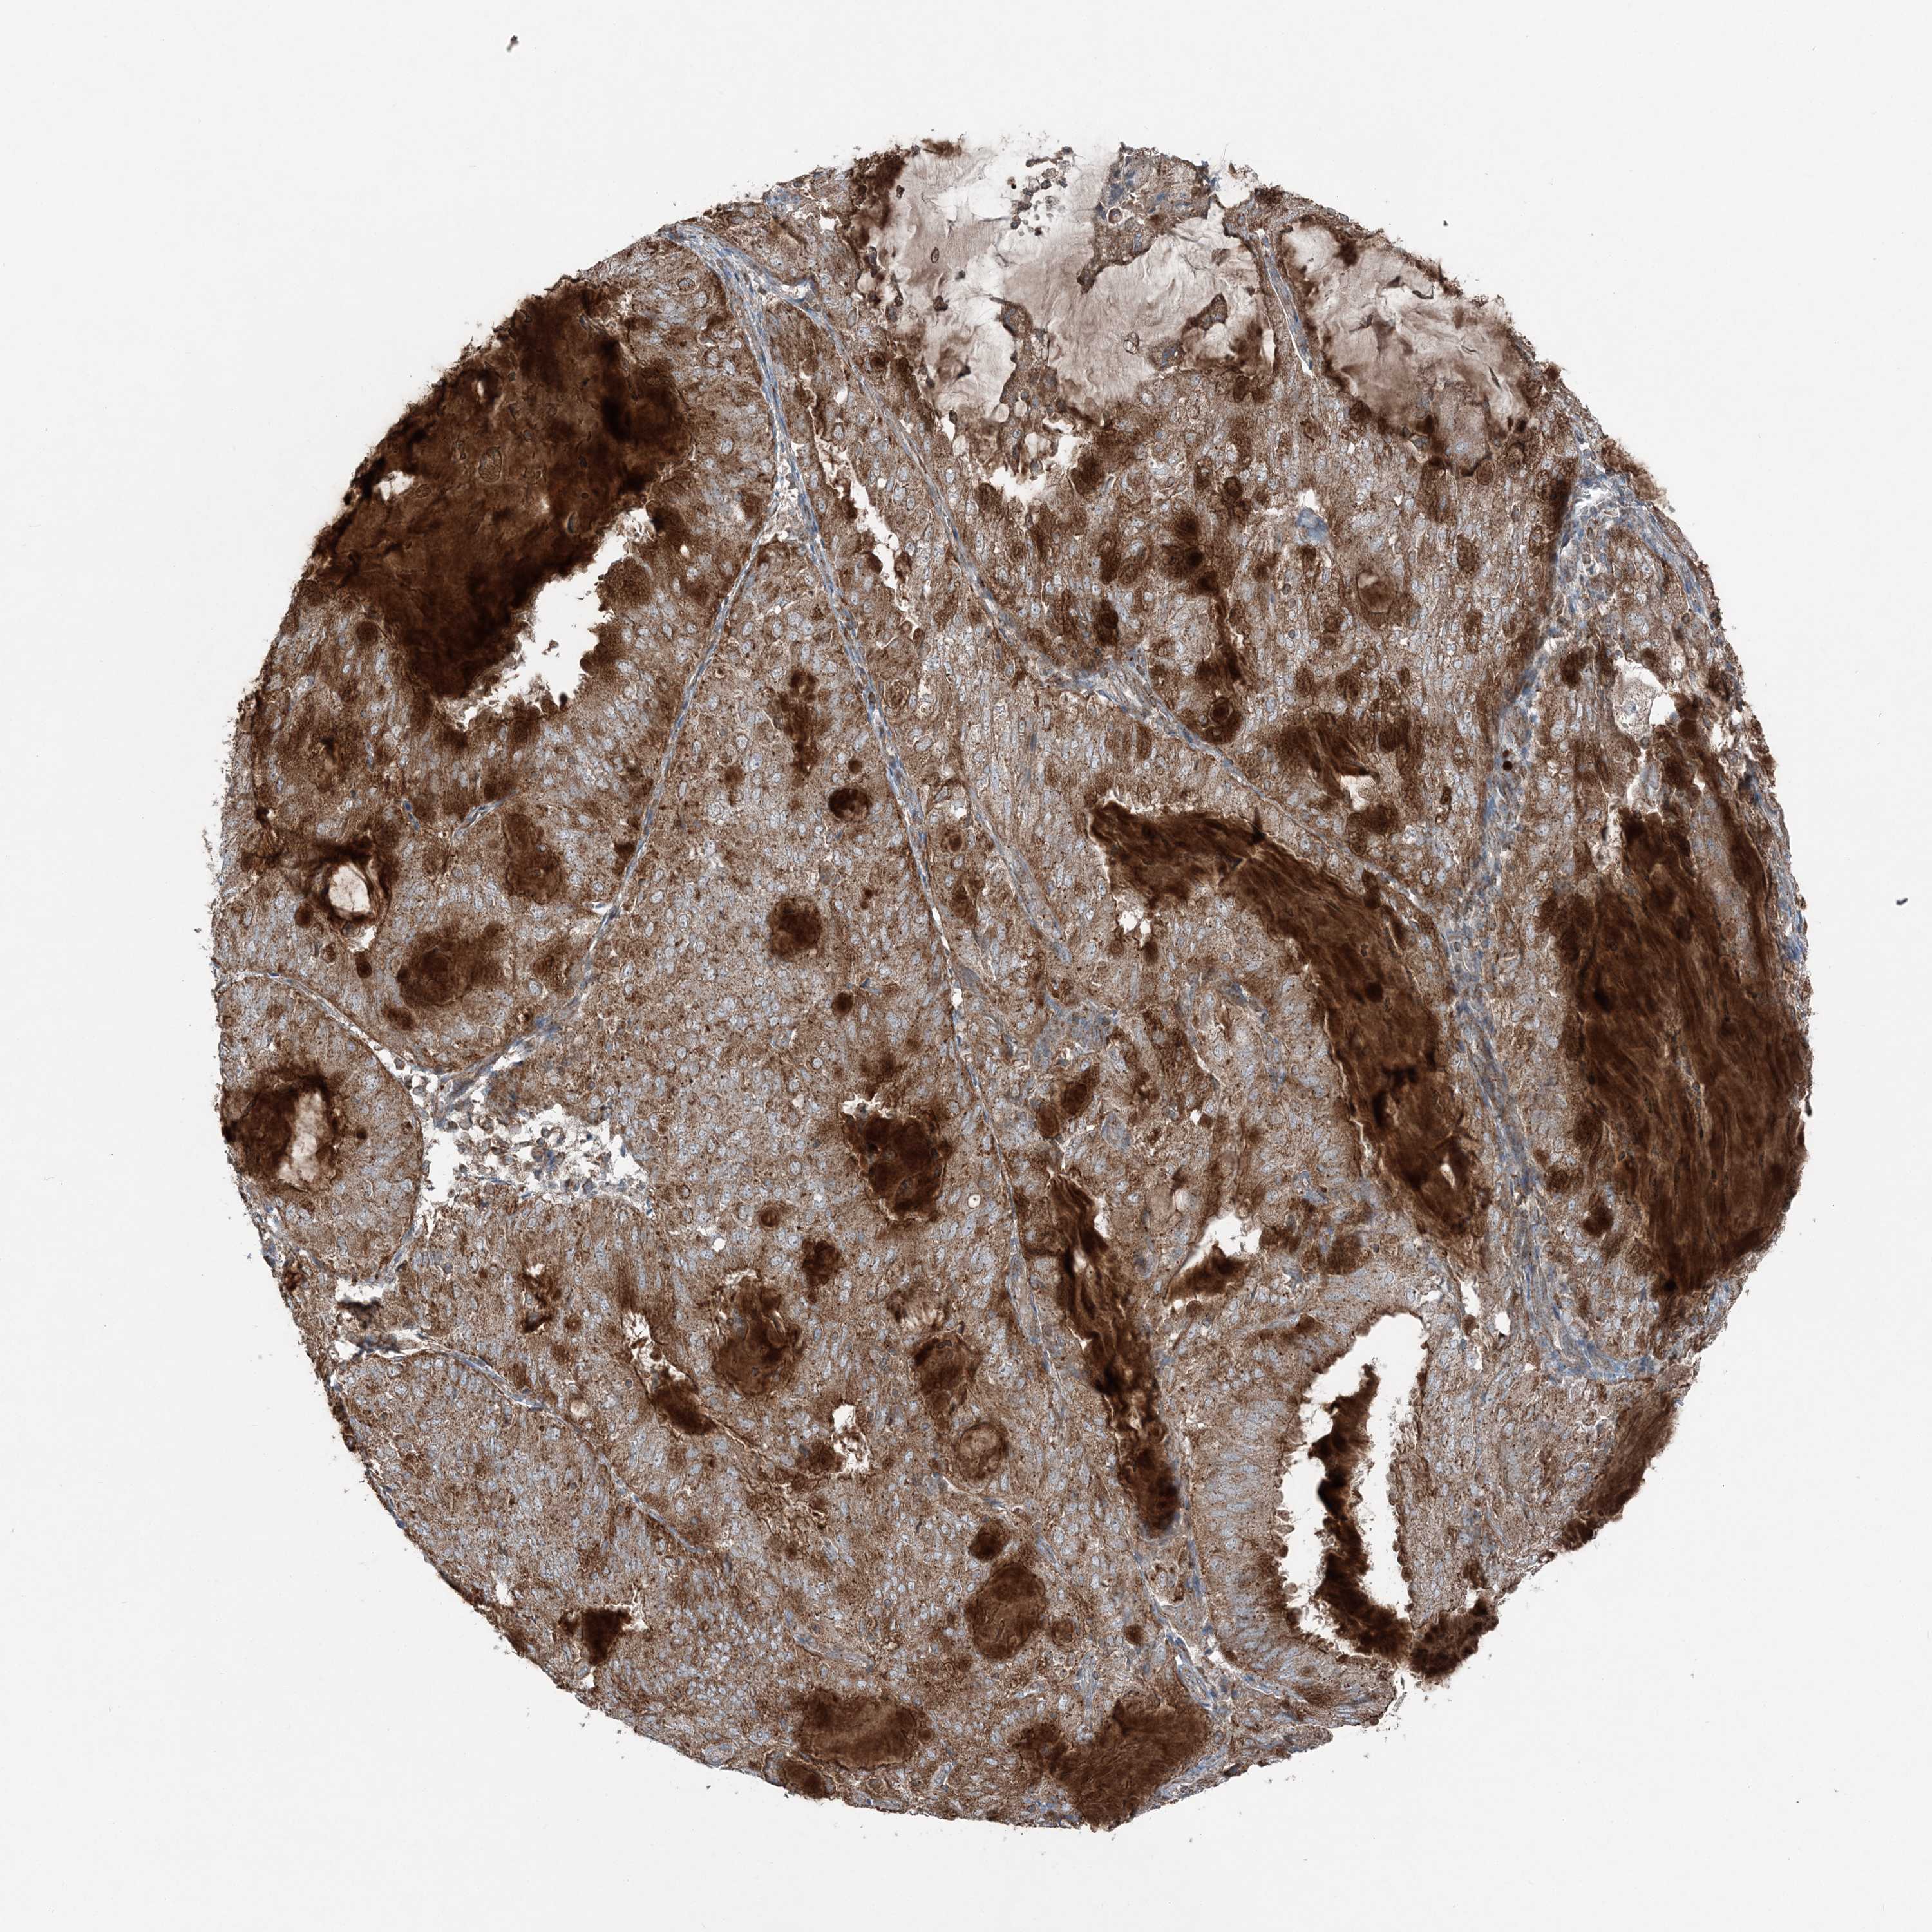

ENDOMETRIAL CANCER - Protein expressioni

A mouse-over function shows sample information and annotation data. Click on an image to view it in a full screen mode. Samples can be filtered based on level of antibody staining by selecting one or several of the following categories: high, medium, low and not detected. The assay and annotation is described here.

Note that samples used for immunohistochemistry by the Human Protein Atlas do not correspond to samples in the TCGA dataset.

Antibody stainingi

Antibody staining in the annotated cell types in the current human tissue is reported as not detected, low, medium, or high, based on conventional immunohistochemistry profiling in selected tissues. This score is based on the combination of the staining intensity and fraction of stained cells.

Each image is clickable and will lead to virtual microscopy that enables deeper exploration of all samples and also displays staining intensity scores, fraction scores and subcellular localization as well as patient and tissue information for each sample.

Antibody HPA036492

Antibody HPA036668

Staining

High

Medium

Low

Not detected

Intensity

Strong

Moderate

Weak

Negative

Quantity

>75%

75%-25%

<25%

None

Location

Nuclear

Cytoplasmic/membranous

Cytoplasmic/membranous,nuclear

Adenocarcinoma, NOS

Adenocarcinoma, metastatic, NOS